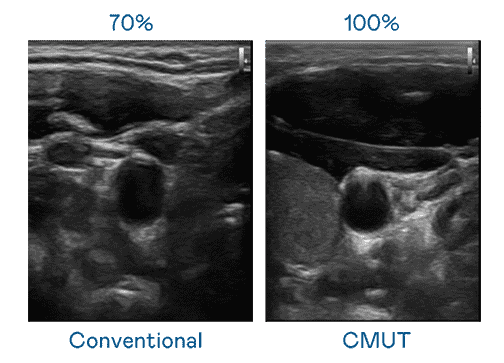

CMUT 技术是一种用电容式微机电元件来产生超音波讯号的技术。。。与传统 PZT 压电式技术相比,,,CMUT 频宽增加 30%,,,更宽频的超音波讯号让影像解析度大幅提升,,,是实现高影像品质医疗超音波扫描、、促进精准医疗发展的关键技术。。

大频宽带来超清晰影像

超音波影像的解析度高低,,,,首先取决于探头能发出的讯号频宽。。。冰球突破 CMUT 可提供高清晰的超音波讯号,,提供高频宽、、、、高灵敏度、、、影像纹理细节更高的超音波影像,,,,协助医护人员缩短影像判读时间及利用精准的医疗影像进行诊断。。